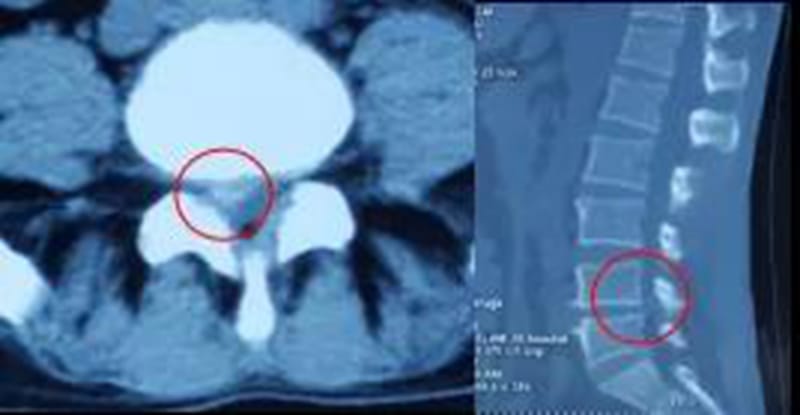

CT:鉴别有无椎间盘突出或突出方向

磁共振(MRI):显示椎管形态,椎间盘有无病变及神经根和脊髓受压情况,有诊断价值。